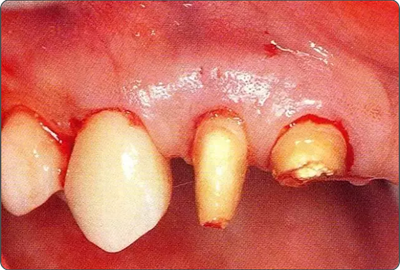

深牙周袋的治療

圖10-4  骨缺損部位進行骨修整結(jié)束的狀態(tài)。

圖10-7  緊密貼合根面讓牙齦復位的狀態(tài)

圖10-8  上頜腭側(cè)處縫合的狀態(tài)。為獲得一次性創(chuàng)傷治愈進行了緊密縫合

圖10-9  術后2周的狀態(tài)。牙齦乳頭獲得保存。較之使用GTR膜,自體骨移植更不容易引起牙齦乳頭的壞死。